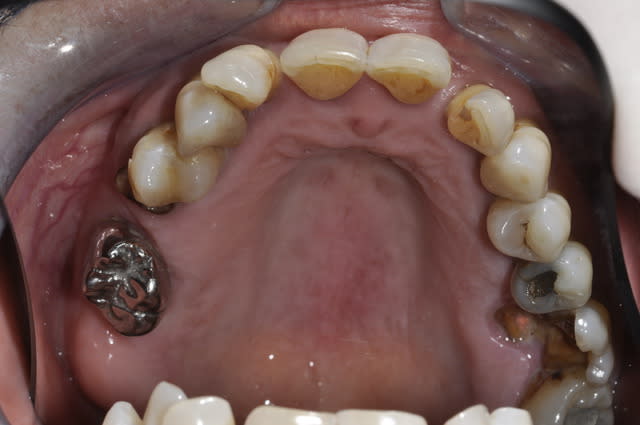

Patiente qui se presente au cabinet car ne supporte plus ses dents.

Pour le maxillaire je lui ai proposé de faire 4 implants + locator + PTotale

ou 6 implants + prothése fixe ( type pilotis). Au choix de la patiente.

Par contre pour la mandibule je sèche un peu.

Est ce que je garde des dents ou pas?

Je pensais peut être garder de 46 à 33 avec assainissement paro et pose de 2 implants en 34/36 avec bridge sur implant.

Ou alors j'extrais tout et je fais une prothése implanto portée?